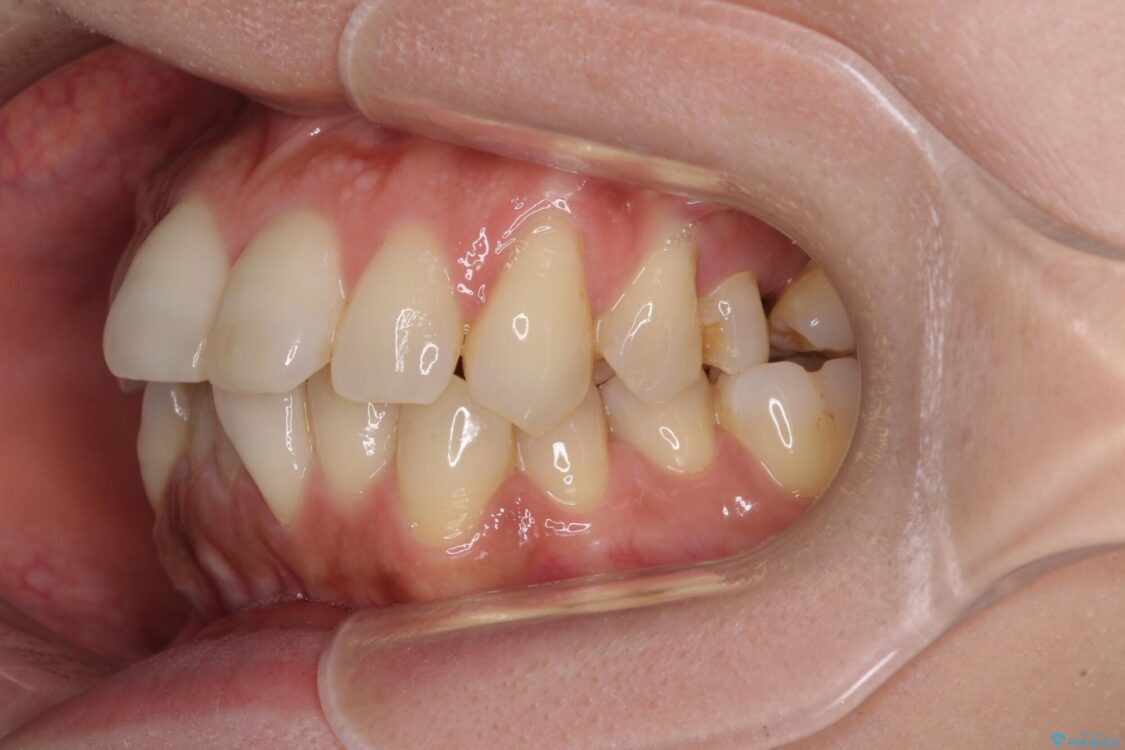

治療前

• インビザラインによる矯正治療と奥歯のインプラント治療 治療前画像

左上第一大臼歯を抜歯した際に、スペースを閉じたそうですが、歯が傾斜してものが挟まって不快とのことでした。

インビザライン矯正で全体の歯列と整えるとともに、左上第一大臼歯部にはスペースを作り、インプラントによる補綴治療を行うこととしました。